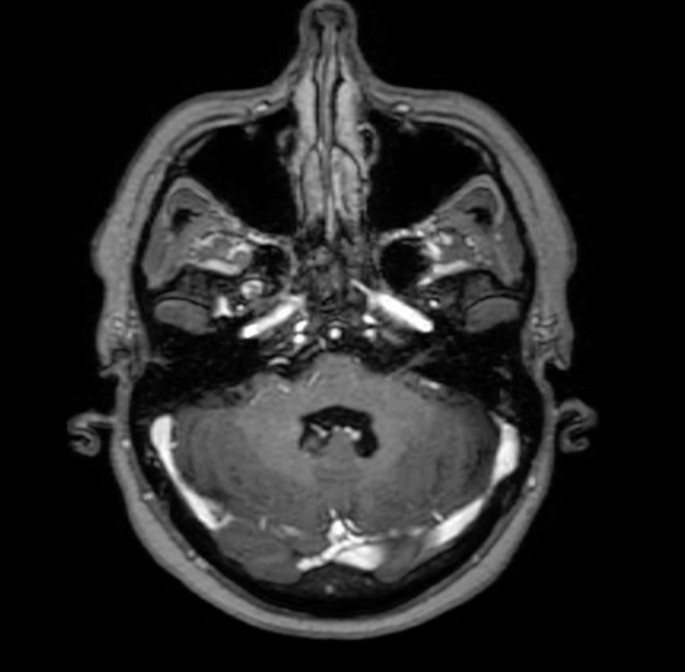

MRI T1 + contrast axial image 3 month after Radiotherapy showing Radiological response compare to Fig. 1.

Radiological response correlated strongly with clinical outcomes, as 90% of patients with neurological improvement or stability showed radiological responses, while all patients with clinical deterioration exhibited radiological progression. Six-month overall survival from the start of re-irradiation was 50%, with progression-free survival at 39.2%.